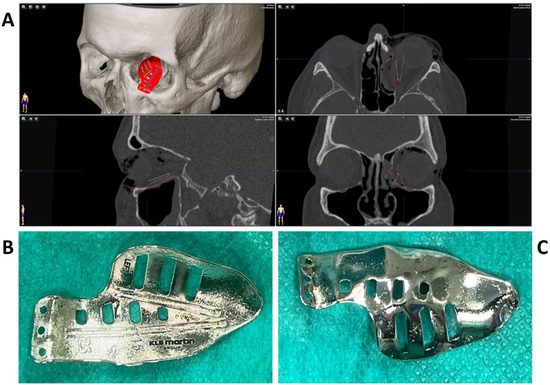

2.2. Surgery